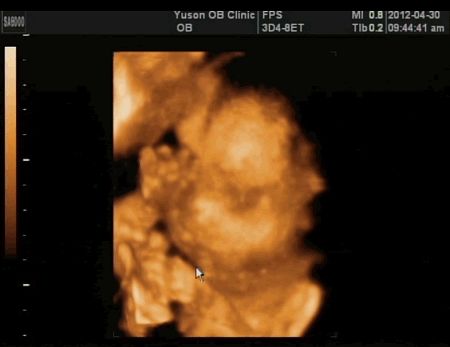

哇唷!胖嘟嘟的腮幫子,看了就好愛!

終於換了一個姿勢,醫生又數了一次他的兩隻手手,有十隻手指,然後看他的耳朵、眼睛、鼻子、嘴巴,然後說:「有看到人中很深喔!這個絕對不可能是兔唇。」

好啦!重點是,怎麼會可愛成這樣啊!

很挺的鼻子喔!以後應該會很帥!希望啦!哈!